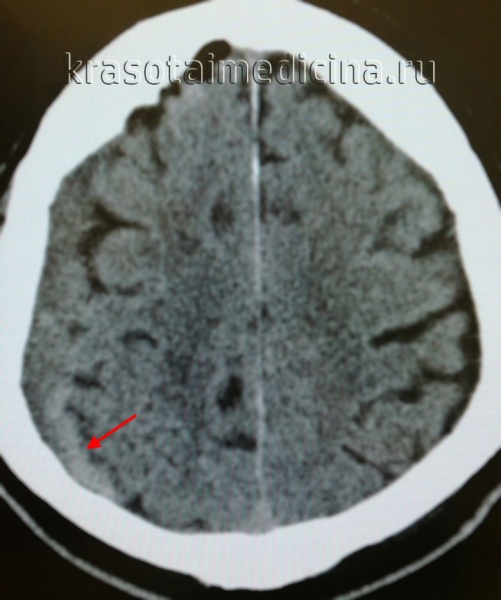

(б) Бесконтрастная КТ, аксиальный срез: у женщины 58 лет с черепно-мозговой травмой определяется классическая острая субдуральная гематома (оСДГ), протягивающаяся над поверхностью левого полушария и компримирующая подлежащее субарахноидальное пространство. Слабовыраженные гиподенсные фокусы на фоне гиперденсной оСДГ соответствуют несвернувшейся крови. При такой картине существует риск быстрот нарастания объема гематомы. (а) Иногда острые субдуральные гематомы (оСДГ) изоденсны по отношению к подлежащей ткани мозга. Обратите внимание на острую субдуральную гематому (оСДГ), обусловливающую масс-эффект, смещение кнутри подлежащею перехода между серым и белым веществом, а также смещение желудочковой системы под серповидный отросток слева направок.

(б) Бесконтрастная КТ, более краниально выполненный срез: у этого же пациента все еще определяется указанная выше изоденсная острая субдуральная гематома (оСДГ). Подлежащие борозды полностью сглажены. Сравните этот симптом «отсутствующих борозд» с нормальными бороздами правого полушария, заполненными ликвором.